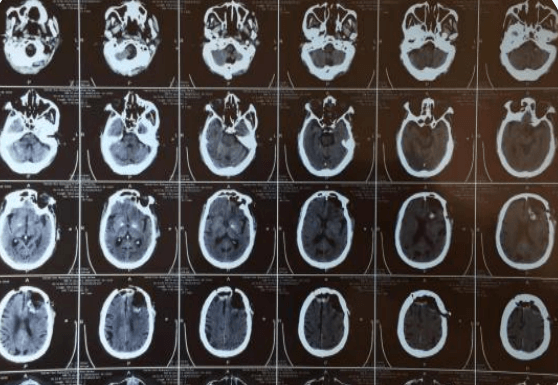

約3個(gè)月前,趙大爺在我院查顱腦CT示:左側(cè)額顳部占位,多考慮腦膜瘤;右側(cè)額部皮下脂肪瘤,當(dāng)時(shí)患者無(wú)明顯癥狀,選擇保守治療,約一周前,患者出現(xiàn)意識(shí)混亂,頭悶表現(xiàn),家屬為求進(jìn)一步治療,解決患者不適,提高患者生活質(zhì)量,入院治療。在劉小雷主任和游文良副主任醫(yī)師的指導(dǎo)下,經(jīng)過(guò)醫(yī)護(hù)一體化協(xié)作模式的共同努力,為78歲高齡的趙大爺術(shù)前制定精準(zhǔn)的手術(shù)方案,術(shù)中在病人家屬的許可下,實(shí)施顯微鏡下顱內(nèi)腫瘤切除術(shù),經(jīng)過(guò)精細(xì)的手術(shù)操作,手術(shù)順利完成,并且一并切除右側(cè)頭皮脂肪瘤,顱內(nèi)外問(wèn)題一起解決,護(hù)理團(tuán)隊(duì)根據(jù)患者病情特點(diǎn)制定了護(hù)理計(jì)劃及護(hù)理措施,密切觀察患者瞳孔意識(shí)變化,肢體活動(dòng)情況,觀察患者生命體征變化,二十四小時(shí)出入量是否平衡,并詳細(xì)的記錄各項(xiàng)指標(biāo)的變化,在護(hù)士專業(yè)而細(xì)致地看護(hù)下,術(shù)后五天,患者無(wú)任何不良反應(yīng),恢復(fù)良好,身體各項(xiàng)指標(biāo)一切正常,無(wú)后遺癥。在神經(jīng)外科二病區(qū)醫(yī)護(hù)團(tuán)隊(duì)的精心治療和護(hù)理下,趙大爺病情日見(jiàn)好轉(zhuǎn),家屬臉上也露出了久違的笑容。